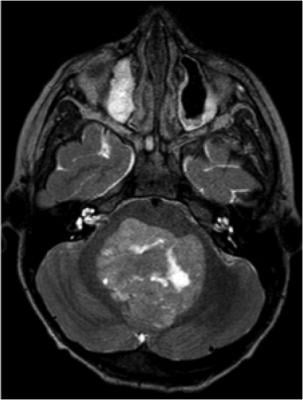

In the study, uptake and background from healthy tissues were estimated on Ga-68 DOTATOC positron emission tomography (PET) scans of 11 meningioma patients and 12 high grade glioma (HGG) patients. A dedicated statistical analysis of the images was completed and validated. The feasibility study was performed using full simulation of emission and detection of the radiation, accounting for the measured uptake and background rate. All meningioma patients but one, who had an atypical extracranial tumor, showed high uptake of DOTATOC. Uptake of Y-90 DOTATOC in meningiomas was high in all studied patients. Uptake in HGGs was lower than in meningiomas but was still acceptable for RGS.

Meningiomas are tumors that grow on the delicate outer covering of the brain. According to the Brain Science Foundation, meningiomas account for approximately 33.8 percent of all primary brain tumors, making them the most common type. Gliomas, which are malignant tumors that commonly invade adjacent tissue and spread through the central nervous system, represent about 17.1 percent of all primary brain tumors and about 70.5 percent of all astrocytomas.